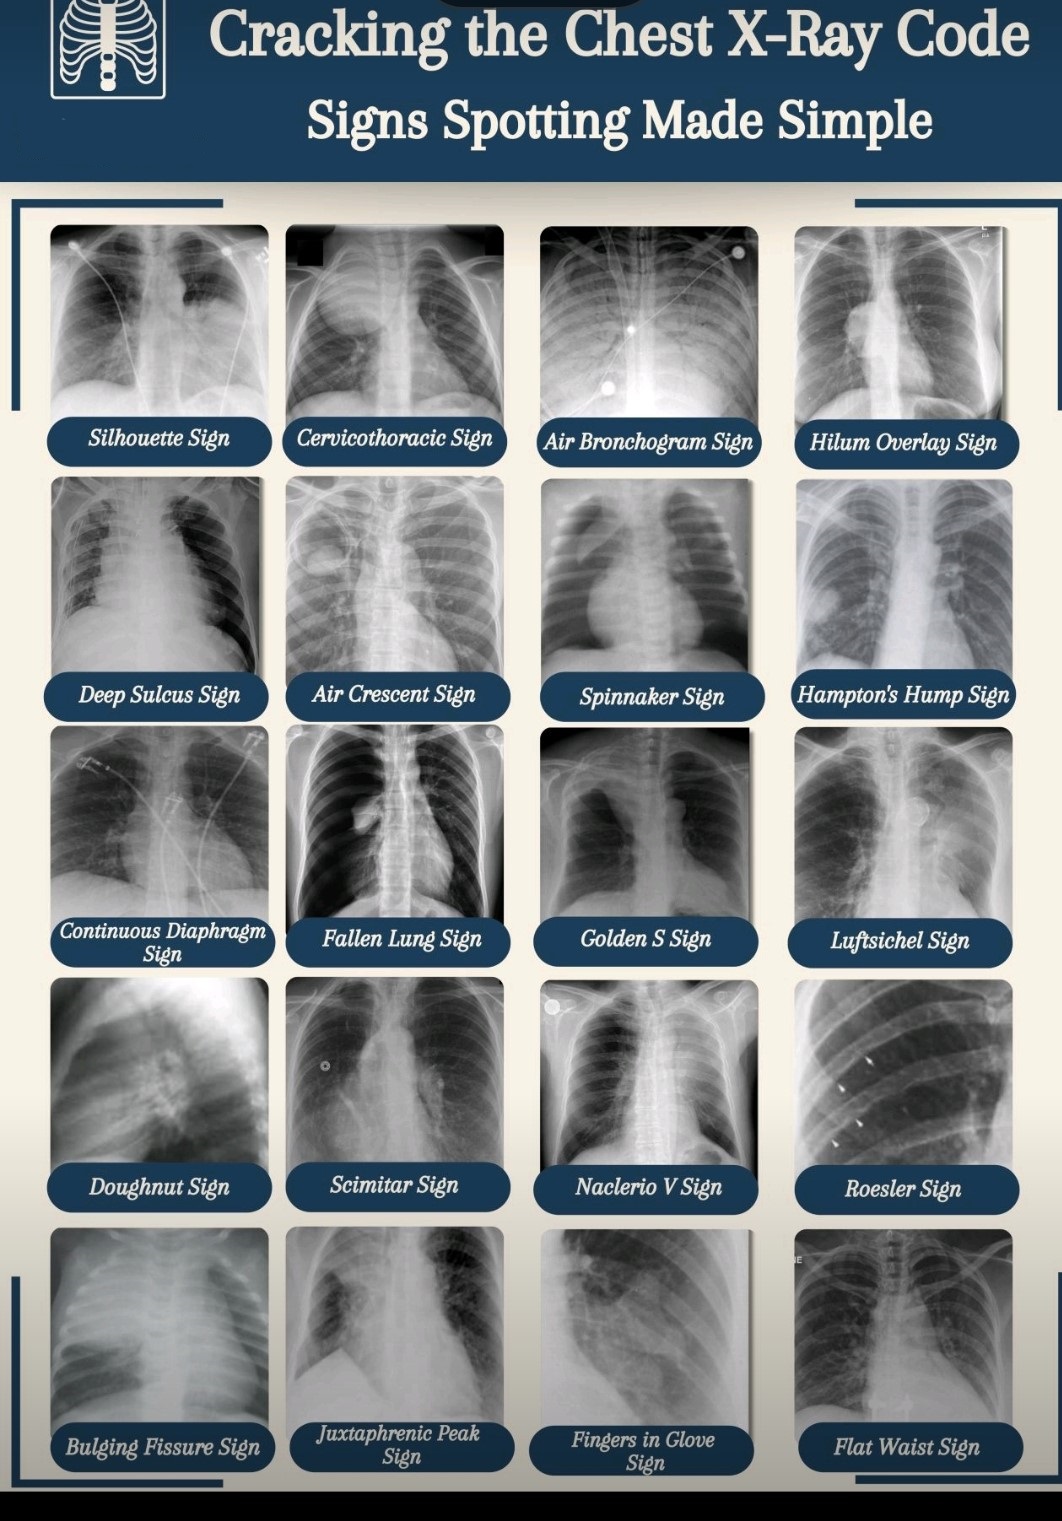

- Consolidation with air bronchograms: Pneumonia.